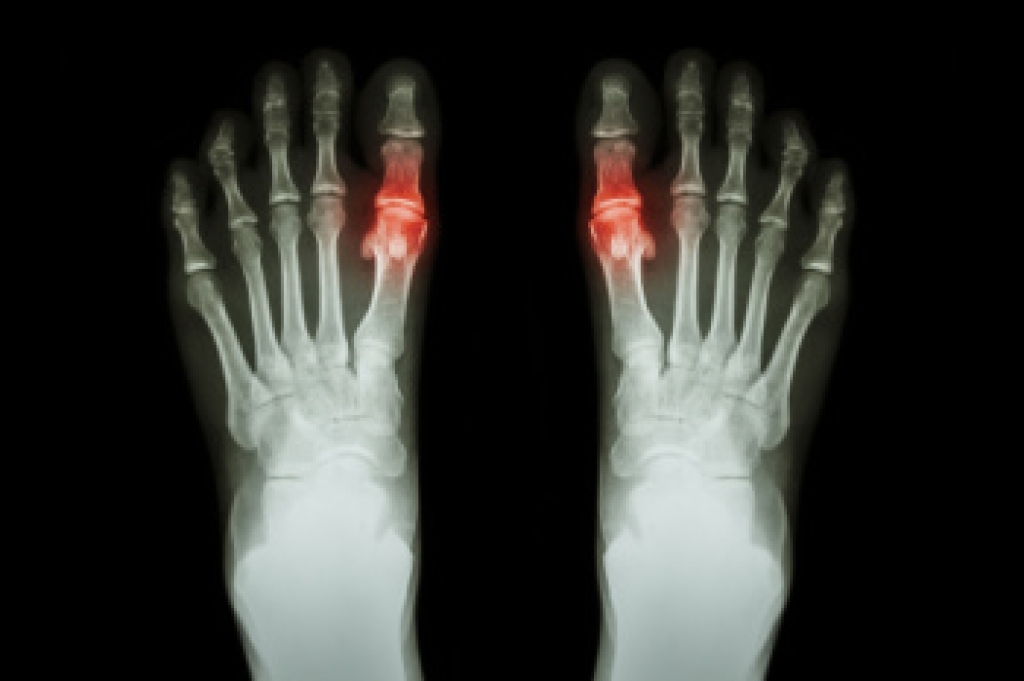

Gout is a form of inflammatory arthritis caused by the buildup of uric acid crystals in the joints, often affecting the big toe. It typically appears suddenly, with symptoms such as intense pain, swelling, redness, and warmth in the affected area. Gout attacks can be triggered by certain foods, excessive alcohol, dehydration, or medications. While lifestyle changes, such as dietary adjustments and increased hydration, can help manage mild cases, recurrent or severe attacks may require medical intervention. If you experience debilitating pain or swelling in the big toe that does not improve on its own, it is important to see a podiatrist. This type of doctor may prescribe medications to lower uric acid levels or reduce inflammation, helping to prevent future flare-ups. If you have or suspect you have gout, it is suggested you schedule an appointment with a podiatrist for a comprehensive evaluation and effective treatment options tailored to your needs.

Gout is a type of arthritis caused by a buildup of uric acid in the bloodstream. It often develops in the foot, especially the big toe area, although it can manifest in other parts of the body as well. Gout can make walking and standing very painful and is especially common in diabetics and the obese.

Gout can easily be identified by redness and inflammation of the big toe and the surrounding areas of the foot. Other symptoms include extreme fatigue, joint pain, and running high fevers. Sometimes corticosteroid drugs can be prescribed to treat gout, but the best way to combat this disease is to get more exercise and eat a better diet.